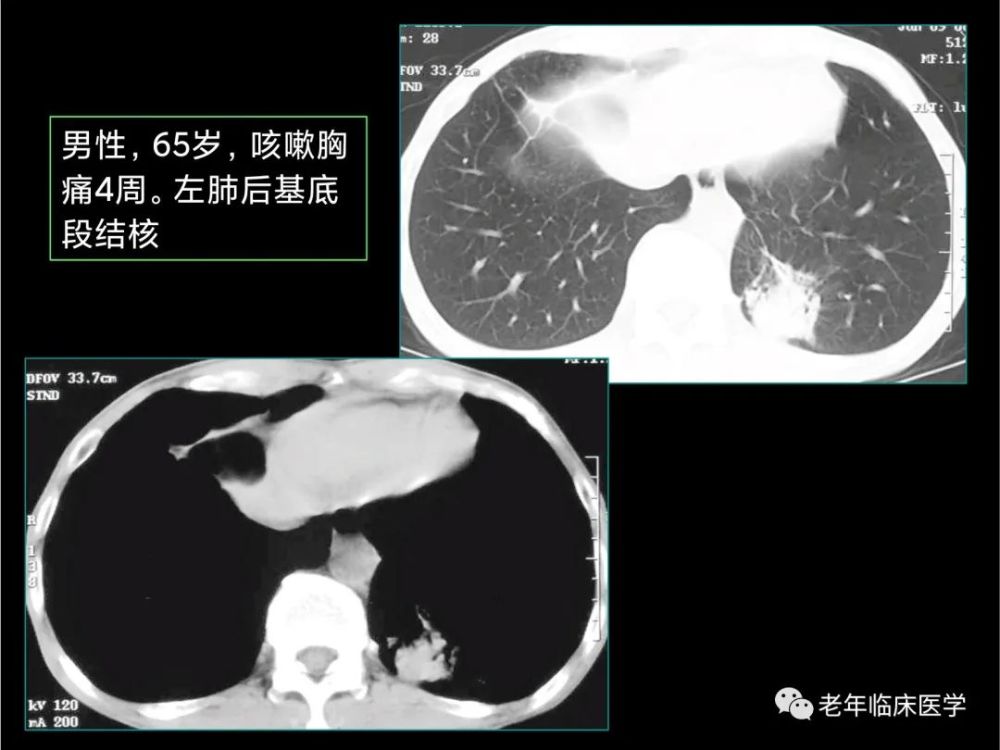

肺结核1例ct影像讨论